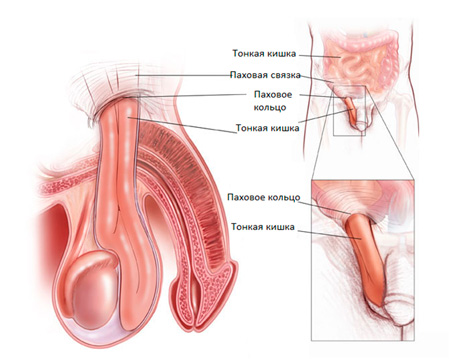

Ábra. Lágyéksérv.

Érdemes megjegyezni, hogy a lágyéksérv nem csak bonyolítja a vízkór, de szintén társbetegség.

Mi veszélyes sérv és szövődményei?

Vékonybél viszonylag mozgatható, így mozoghat a lágyéki csatornát a herezacskóba. Ha visszajön simán, akkor ezt nevezzük a mellkasban csökkenti a. Idővel ez a folyamat lehet gátolt, és a belek már nem olyan könnyen vissza a hasüregbe, a sérv válik nevpravlyaemoy. A legveszélyesebb strangulated sérv. Általában ez történik a háttérben a fizikai aktivitás, székrekedés vagy puffadás. Due megsértése zavarhatja vérellátás bél rész található a csatorna, ami szélsőséges esetben meg lehet szüntetni elsorvadása bél hurkok és nehéz művelet hosszú gyógyulási időszak.